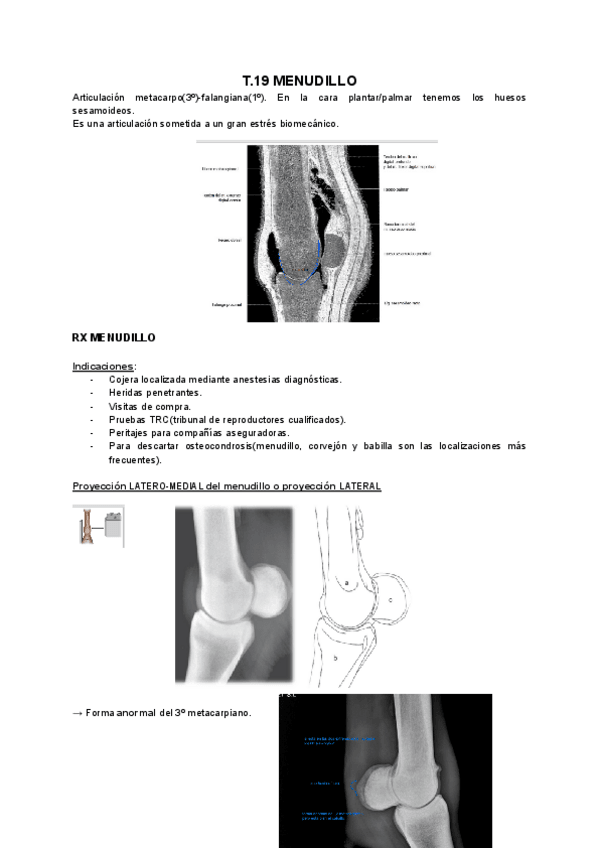

MENUDILLO-Y-METATARSO.pdf

14 páginas